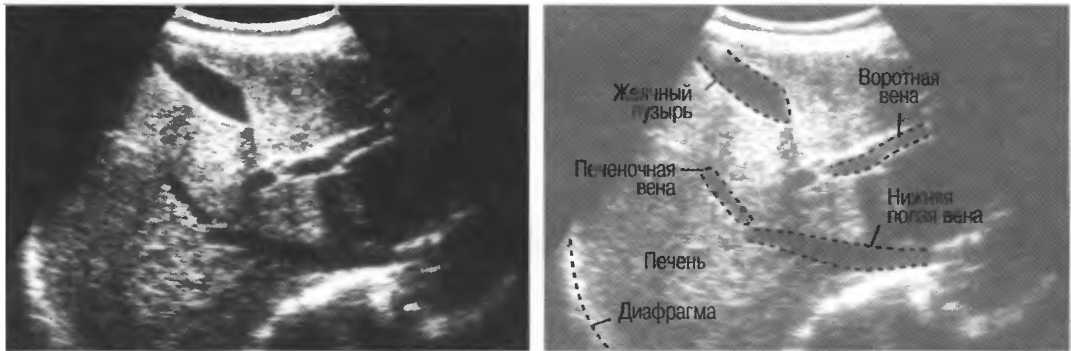

- Печеночные вены диаметром всего 3 мм должны визуализироваться при сканировании под углом 45° к поверхности нормальной печени (рис. 25).

Рис.25. Аппарат хорошего качества должен позволять визуализировать печеночные вены диаметром 3 мм. Этот тест может регулярно использоваться для контроля качества изображения.